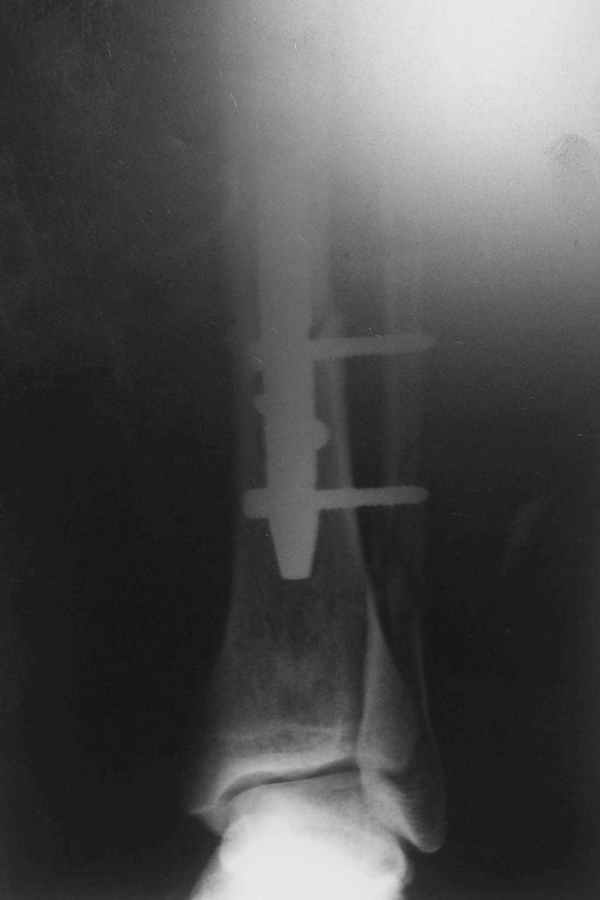

Рентгенограмы

Не удается отправить первичные снимки. А что скажите по имеющимся?!

Выполненный остосинтез нестабилен. Штифт надо заменить по "размеру" на солидный, дистльно три запирающих винта. Успехов!

Перелом спиральный, то есть низкоэнергетический, так что со сращением дело обстоит уже неплохо, лишь бы "костоеда" не развилась. Отломки выглядят уже стабилизированными костной мозолью, так что довводить винты, наверно, уже незачем. Разве что при клинической оценке подвижность еще есть - тогда можно для стабилизации наложить простейший аппарат, не опасаясь контакта его элементов с гвоздем, поскольку места в дистальном метафизе оставлено более чем достаточно.

С Александром согласен, нет необходимости делать дополнительные усилия для сращения, не большая компрессия аппаратом из двух колец и полная нагрузка доделает работу.